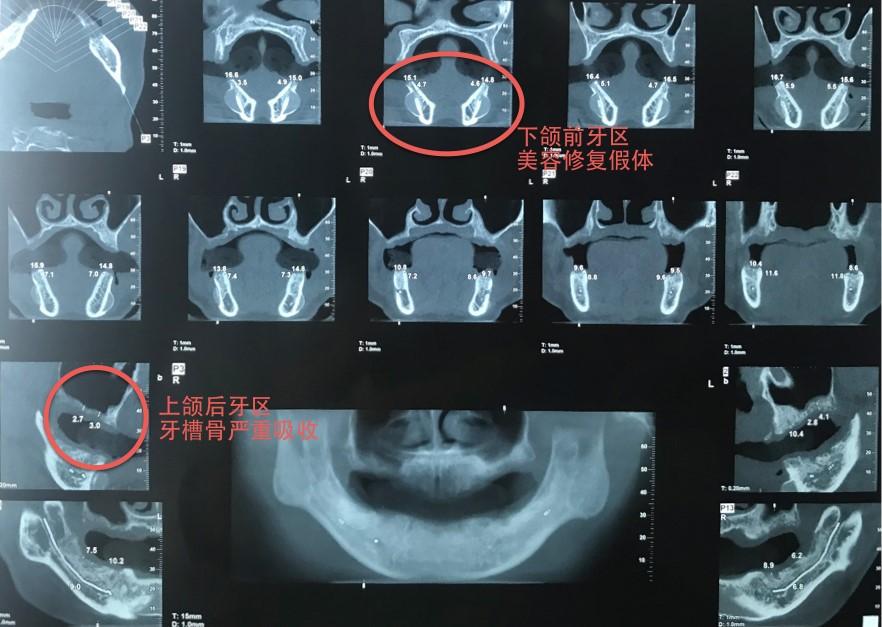

近日,南京醫(yī)科大學(xué)附屬口腔醫(yī)院暨江蘇省口腔醫(yī)院口腔種植科聯(lián)合口腔頜面外科完成一例復(fù)雜、疑難病例——全程數(shù)字化指導(dǎo)下的穿顴種植修復(fù)。患者馬女士,51歲,初來該院時由口腔種植科湯春波主任接診,檢查發(fā)現(xiàn)其口內(nèi)余留牙全部松動,牙結(jié)石覆蓋大部分牙面,已無法正常咀嚼,嚴(yán)重影響生活質(zhì)量,先指導(dǎo)其于該院口腔頜面外科拔除全部余留松動牙。拔牙2個多月后,對患者重新進(jìn)行口內(nèi)及影像學(xué)檢查,CBCT顯示患者上頜牙槽骨嚴(yán)重缺損,右側(cè)后牙區(qū)可用骨高度不到3 mm,前牙區(qū)牙槽骨像雞蛋殼一樣薄、脆,而下頜前牙區(qū)還留有數(shù)年前的美容充填假體。在此基礎(chǔ)上進(jìn)行傳統(tǒng)種植,就如同在刀尖上行走,需要進(jìn)行繁復(fù)的植骨手術(shù),手術(shù)創(chuàng)傷極大。

術(shù)前CBCT檢查